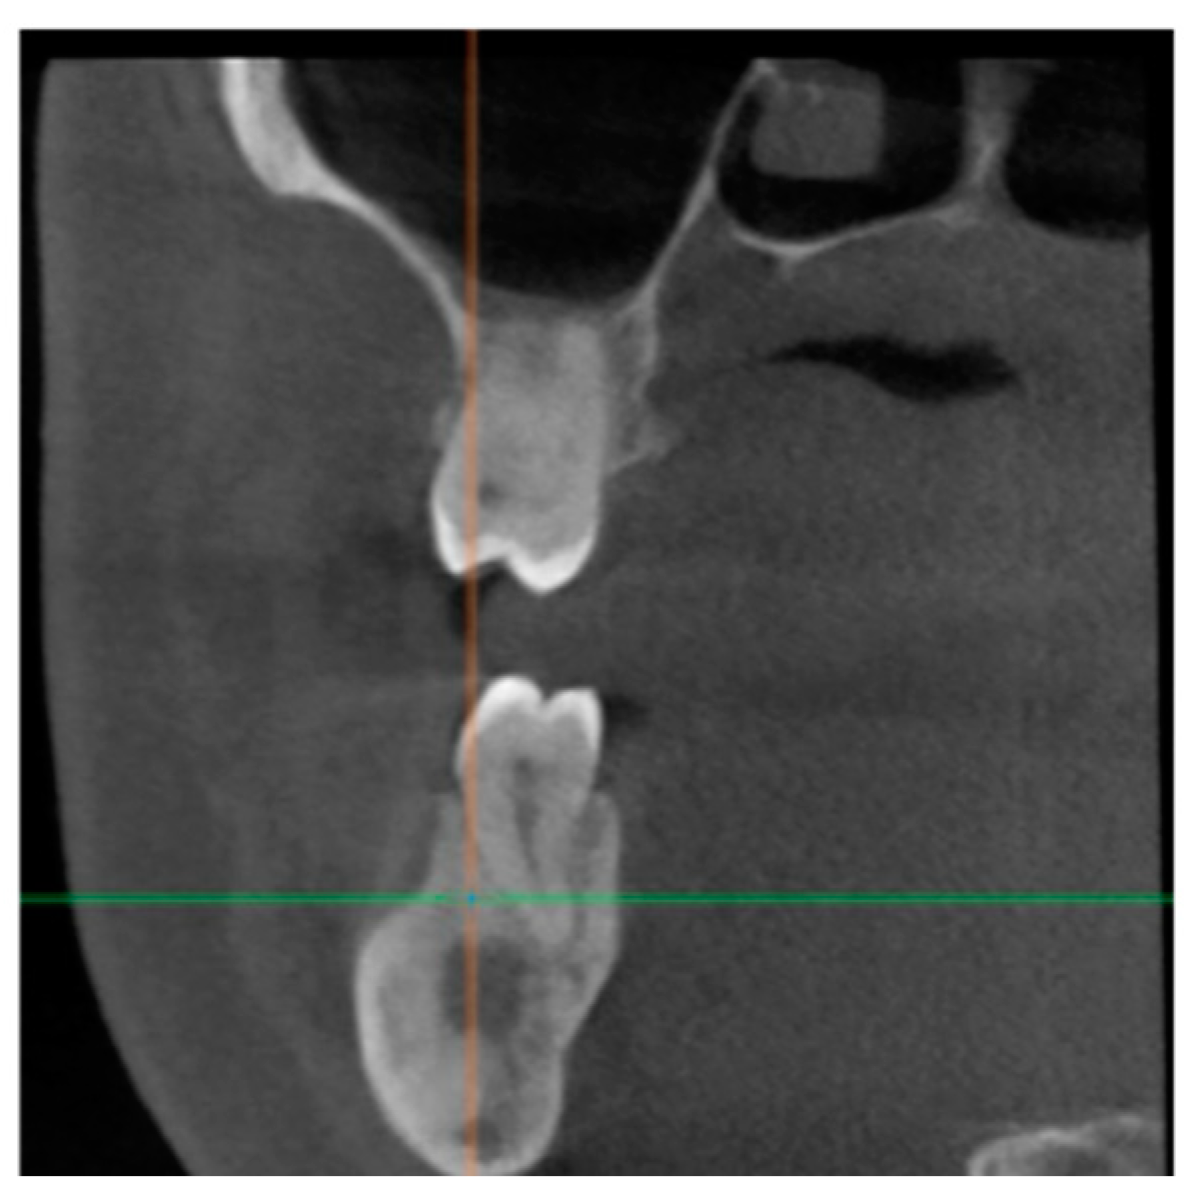

2. Case Presentation